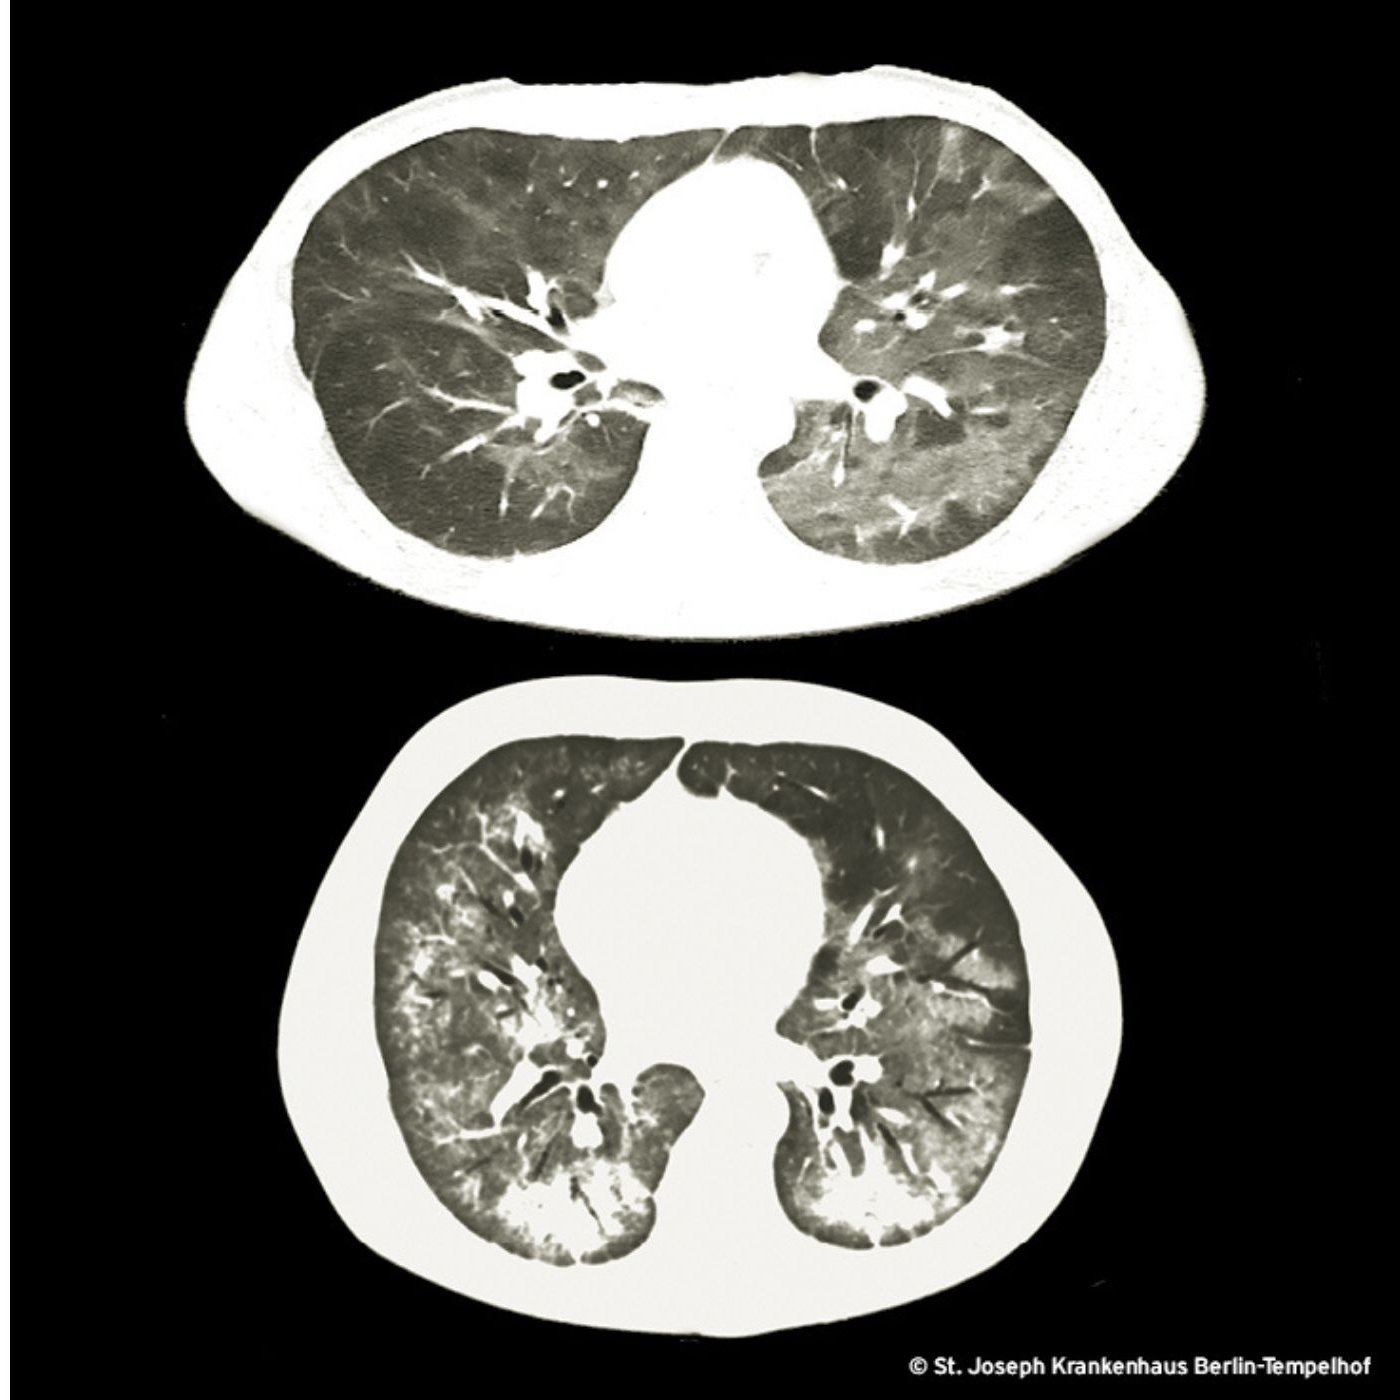

Die pulmonale Auskultation ist bei der PcP unauffällig (genauso wie das konventionelle Thoraxbild welches in ca. 30% der Fälle als normal befundet wird). Soorstomatitis und Sooroesophagitis sind regelmäßige Begleiter der PcP und gleichzeitig starke HIV-Indikatoren, weshalb sie bei Patient*innen mit Fieber, Gewichtsverlust, Leistungsminderung mit oder ohne Lutfnot und Husten die Alarmglocken erklingen lassen müssen.